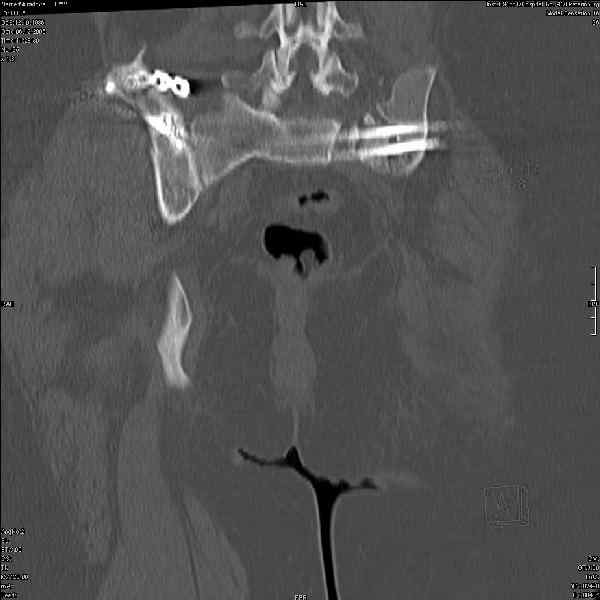

Молодая девушка 19 лет, травма 1 год назад, тогда же прооперирована.

В настоящее время имеются ноющие боли в области крестца слева, нарушение походки, ощущение неуверенности, слабости в левой нижней конечности, неврологически -непостоянные парестезии в левой нижней конечности. Ходит с дополнительной опорой, страдает от ожирения.

В приложении снимки при поступлении и послеоперационные год назад.

Могу сказать одно: миграция винтов и нестабильность синтеза левого подвздошно-крестцовогоо сочленения очевидна.